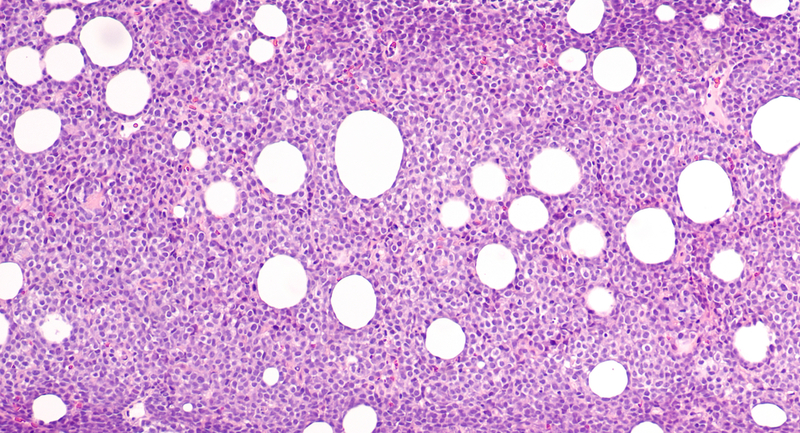

Checkpoint blockade therapy is effective in several tumour types, but generally ineffective in non-Hodgkin's lymphomas. The study's findings suggest that when this immunotherapy is combined with a stem cell transplant, which the researchers call "immunotransplant", the process ramps up the T cells to increase the cancer-killing immune response tenfold, allowing it to be effective for non-Hodgkin's lymphoma and more successful for melanoma and lung cancer.

The transplant works by "making space" for re-infused immune cells (T cells) to proliferate by clearing out a patient's original immune system. While they are proliferating and building the immune system back up, they become activated, and the anti-tumour T cells' anti-cancer effect becomes stronger.